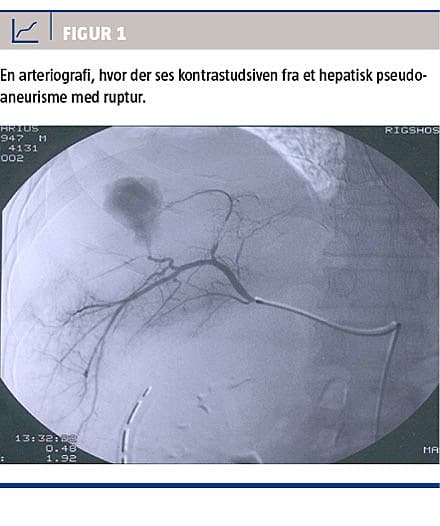

Diagnosen stilles med enten arteriografi, CT med i.v. kontrast (CT-angiografi) eller UL-skanning med Doppler [1]. Arteriografi benyttes sjældent i den initiale diagnostik af HPA, men er til gengæld en del af behandlingen ved TAE. CT-angiografi er ofte førstevalg til diagnosticering af HPA. Med CT-angiografi visualiseres blodkarrene, og den kan optages i både arteriel og venøs fase. Diagnosticering af HPA foretages i den arterielle fase, hvor pseudoaneurismet ses som en kontrastfyldt kavitet ved siden af donorarterien. Ofte ses der et forbindelsesled, selve »halsen«, mellem arterien og pseudoaneurismet.

Er der hul på pseudoaneurismet, vil dette vise sig som kontrastudsiven (ekstravasation) i det omkringliggende væv [1, 18] (Figur 1). UL-skanning med Doppler-flow kan også anvendes i diagnostikken af HPA [3, 18]. Her eftersøger man en turbulent blodstrøm, et såkaldt »yin-yang-tegn«, der viser sig som et rødt/blåt farvemiks langs et blodkar med ensrettet blodgennemstrømning. UL-skanning kan også suppleres med i.v. kontrast (contrast-enhanced ultra sound (CEUS)), men dette er endnu ikke vanlig praksis i Danmark. Flere internationale undersøgelser viser

Taksigelse: Susanne Frevert takkes for Figur 1.